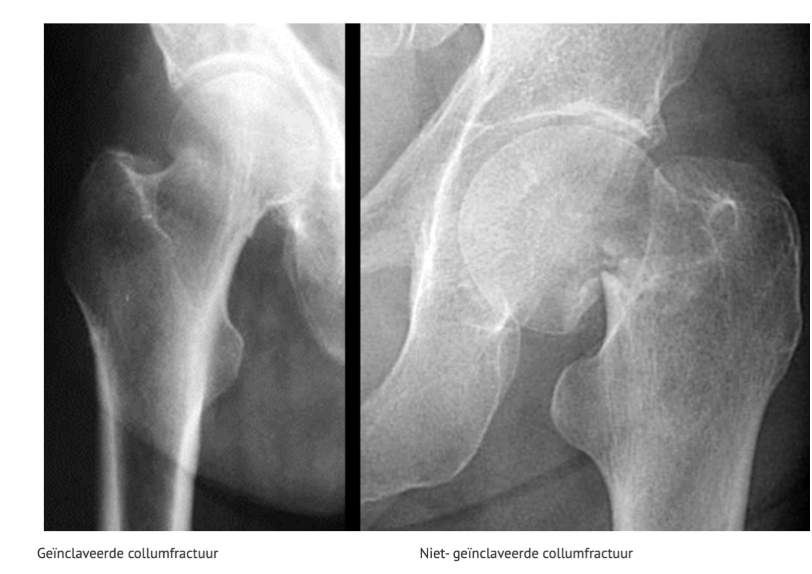

COLLUM FEMORIS FRACTUUR

I: incompleet

II: compleet, niet verplaatst

III: mild verplaatst

IV: volledig verplaatst

Groot risico bij deze fractuur→Kopnecrose (slechte doorbloeding).

Geïnclaveerde fractuur

fractuur waarbij delen van de fractuur in elkaar gedrukt worden.

Bij mediale collumfractuur kan de femurkop loslaten van de femurhals, waardoor de femur zelf naar craniaal geduwt wordt en er een geinclaveerde fractuur ontstaat